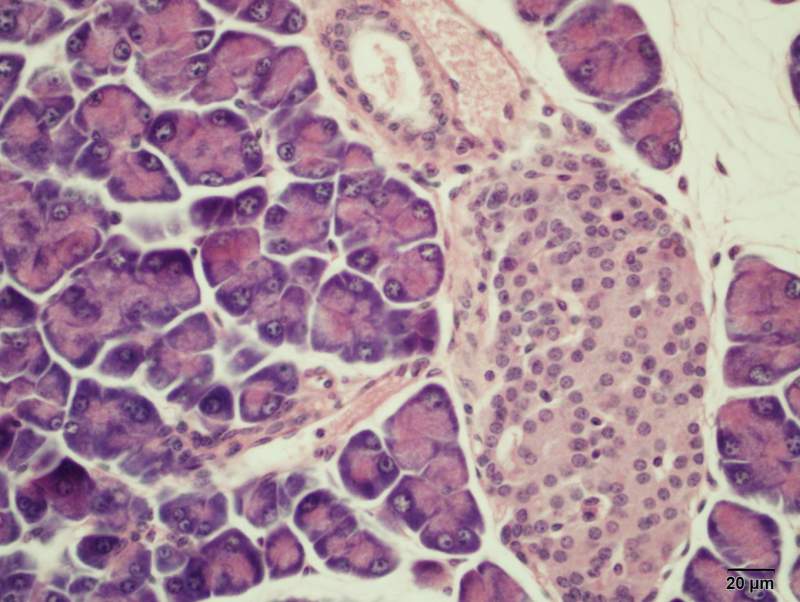

小鼠胰岛特殊染色,醛-品红方法,染出来细胞核为什么是绿色的啊.... 已有1人参与